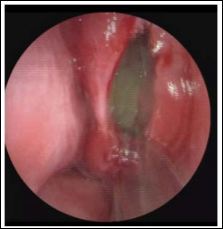

The treatment was based on a total surgical removal under general anesthesia. During the surgery, was discovered a voluminous mass, with a regular aspect, on the left middle turbinate, going continuously with its mucosa. The structure was opened exposing a cavity into the middle turbinate with pus flowing. The instrumental excision of the mass was performed with a middle meatotomy, a total ethmoidectomy and a right sphenoidotomy, in order to permit the sinus draining (Figure 2)

Figure 2: 3D endoscopic image showing the concha bullosa opened exposing a cavity into the middle turbinate with pus flowing.